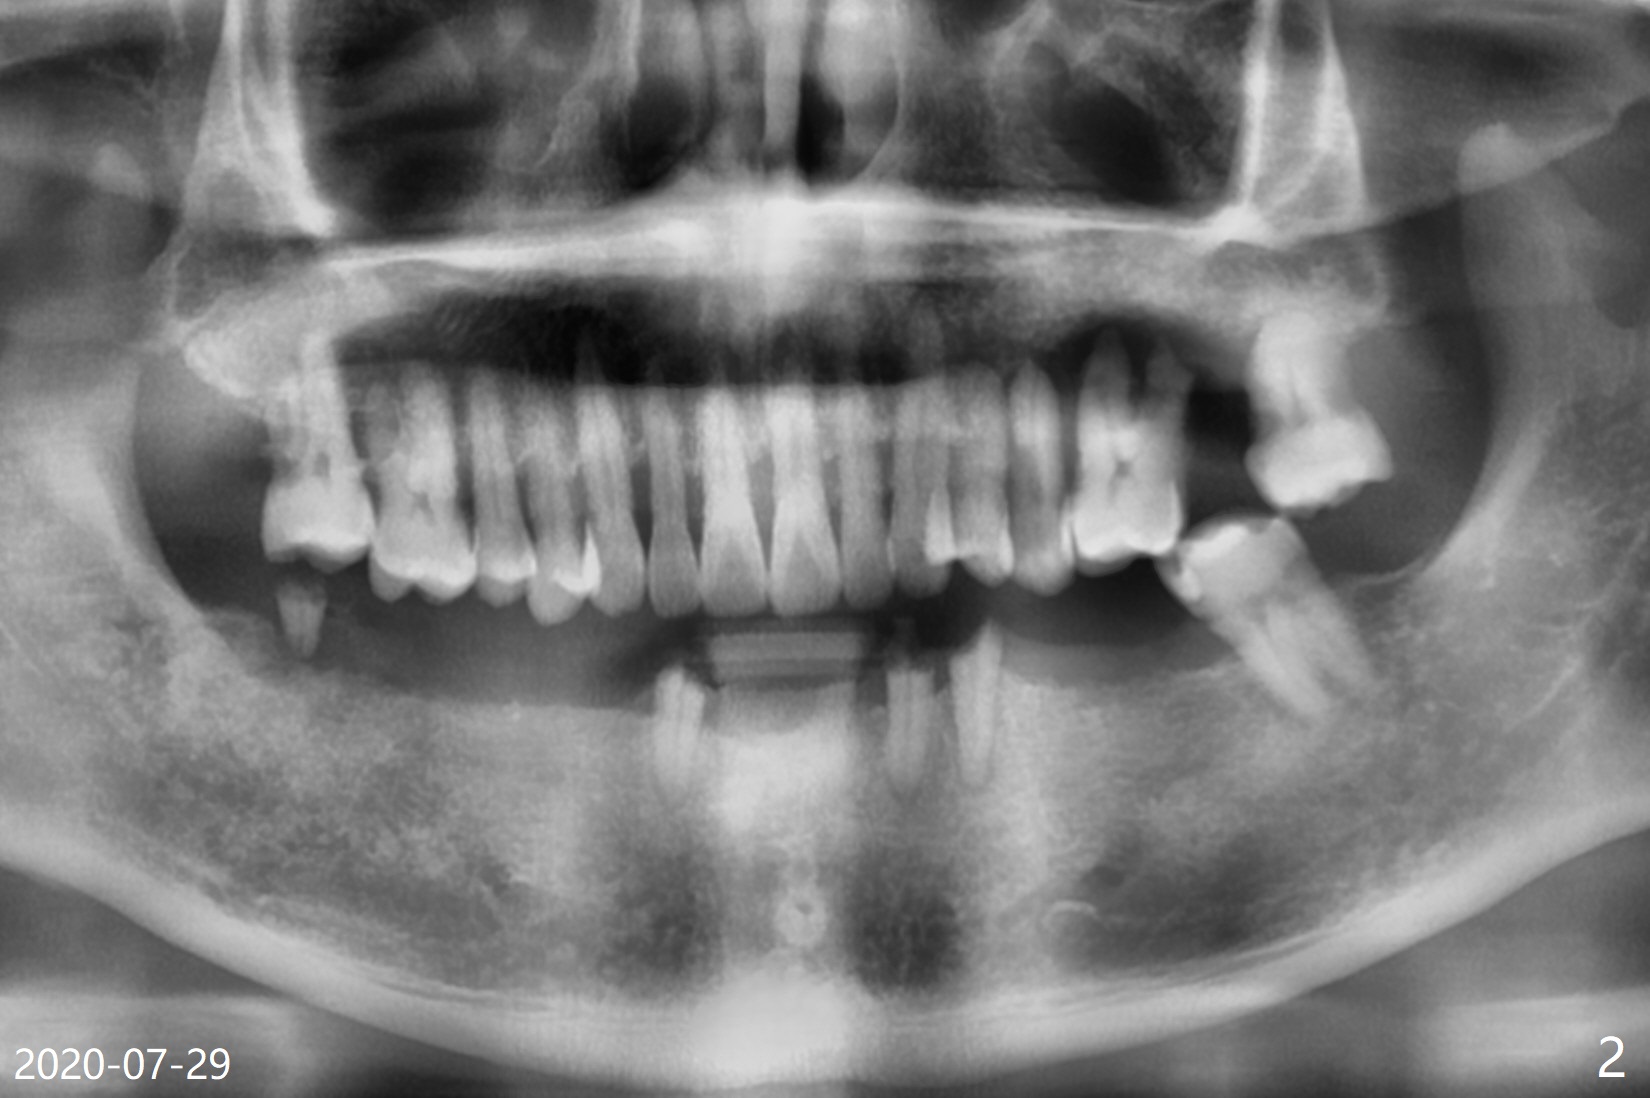

60岁男两年中牙齿状态变化大(图一,二)。上颌深洗时,只同意拔除左上第一磨牙,后者腭侧(图三P)和远中颊侧(DB)牙槽窝特别浅,而近中颊侧大而深(MB),需要做位点保留吗?只在近中颊侧窝做?